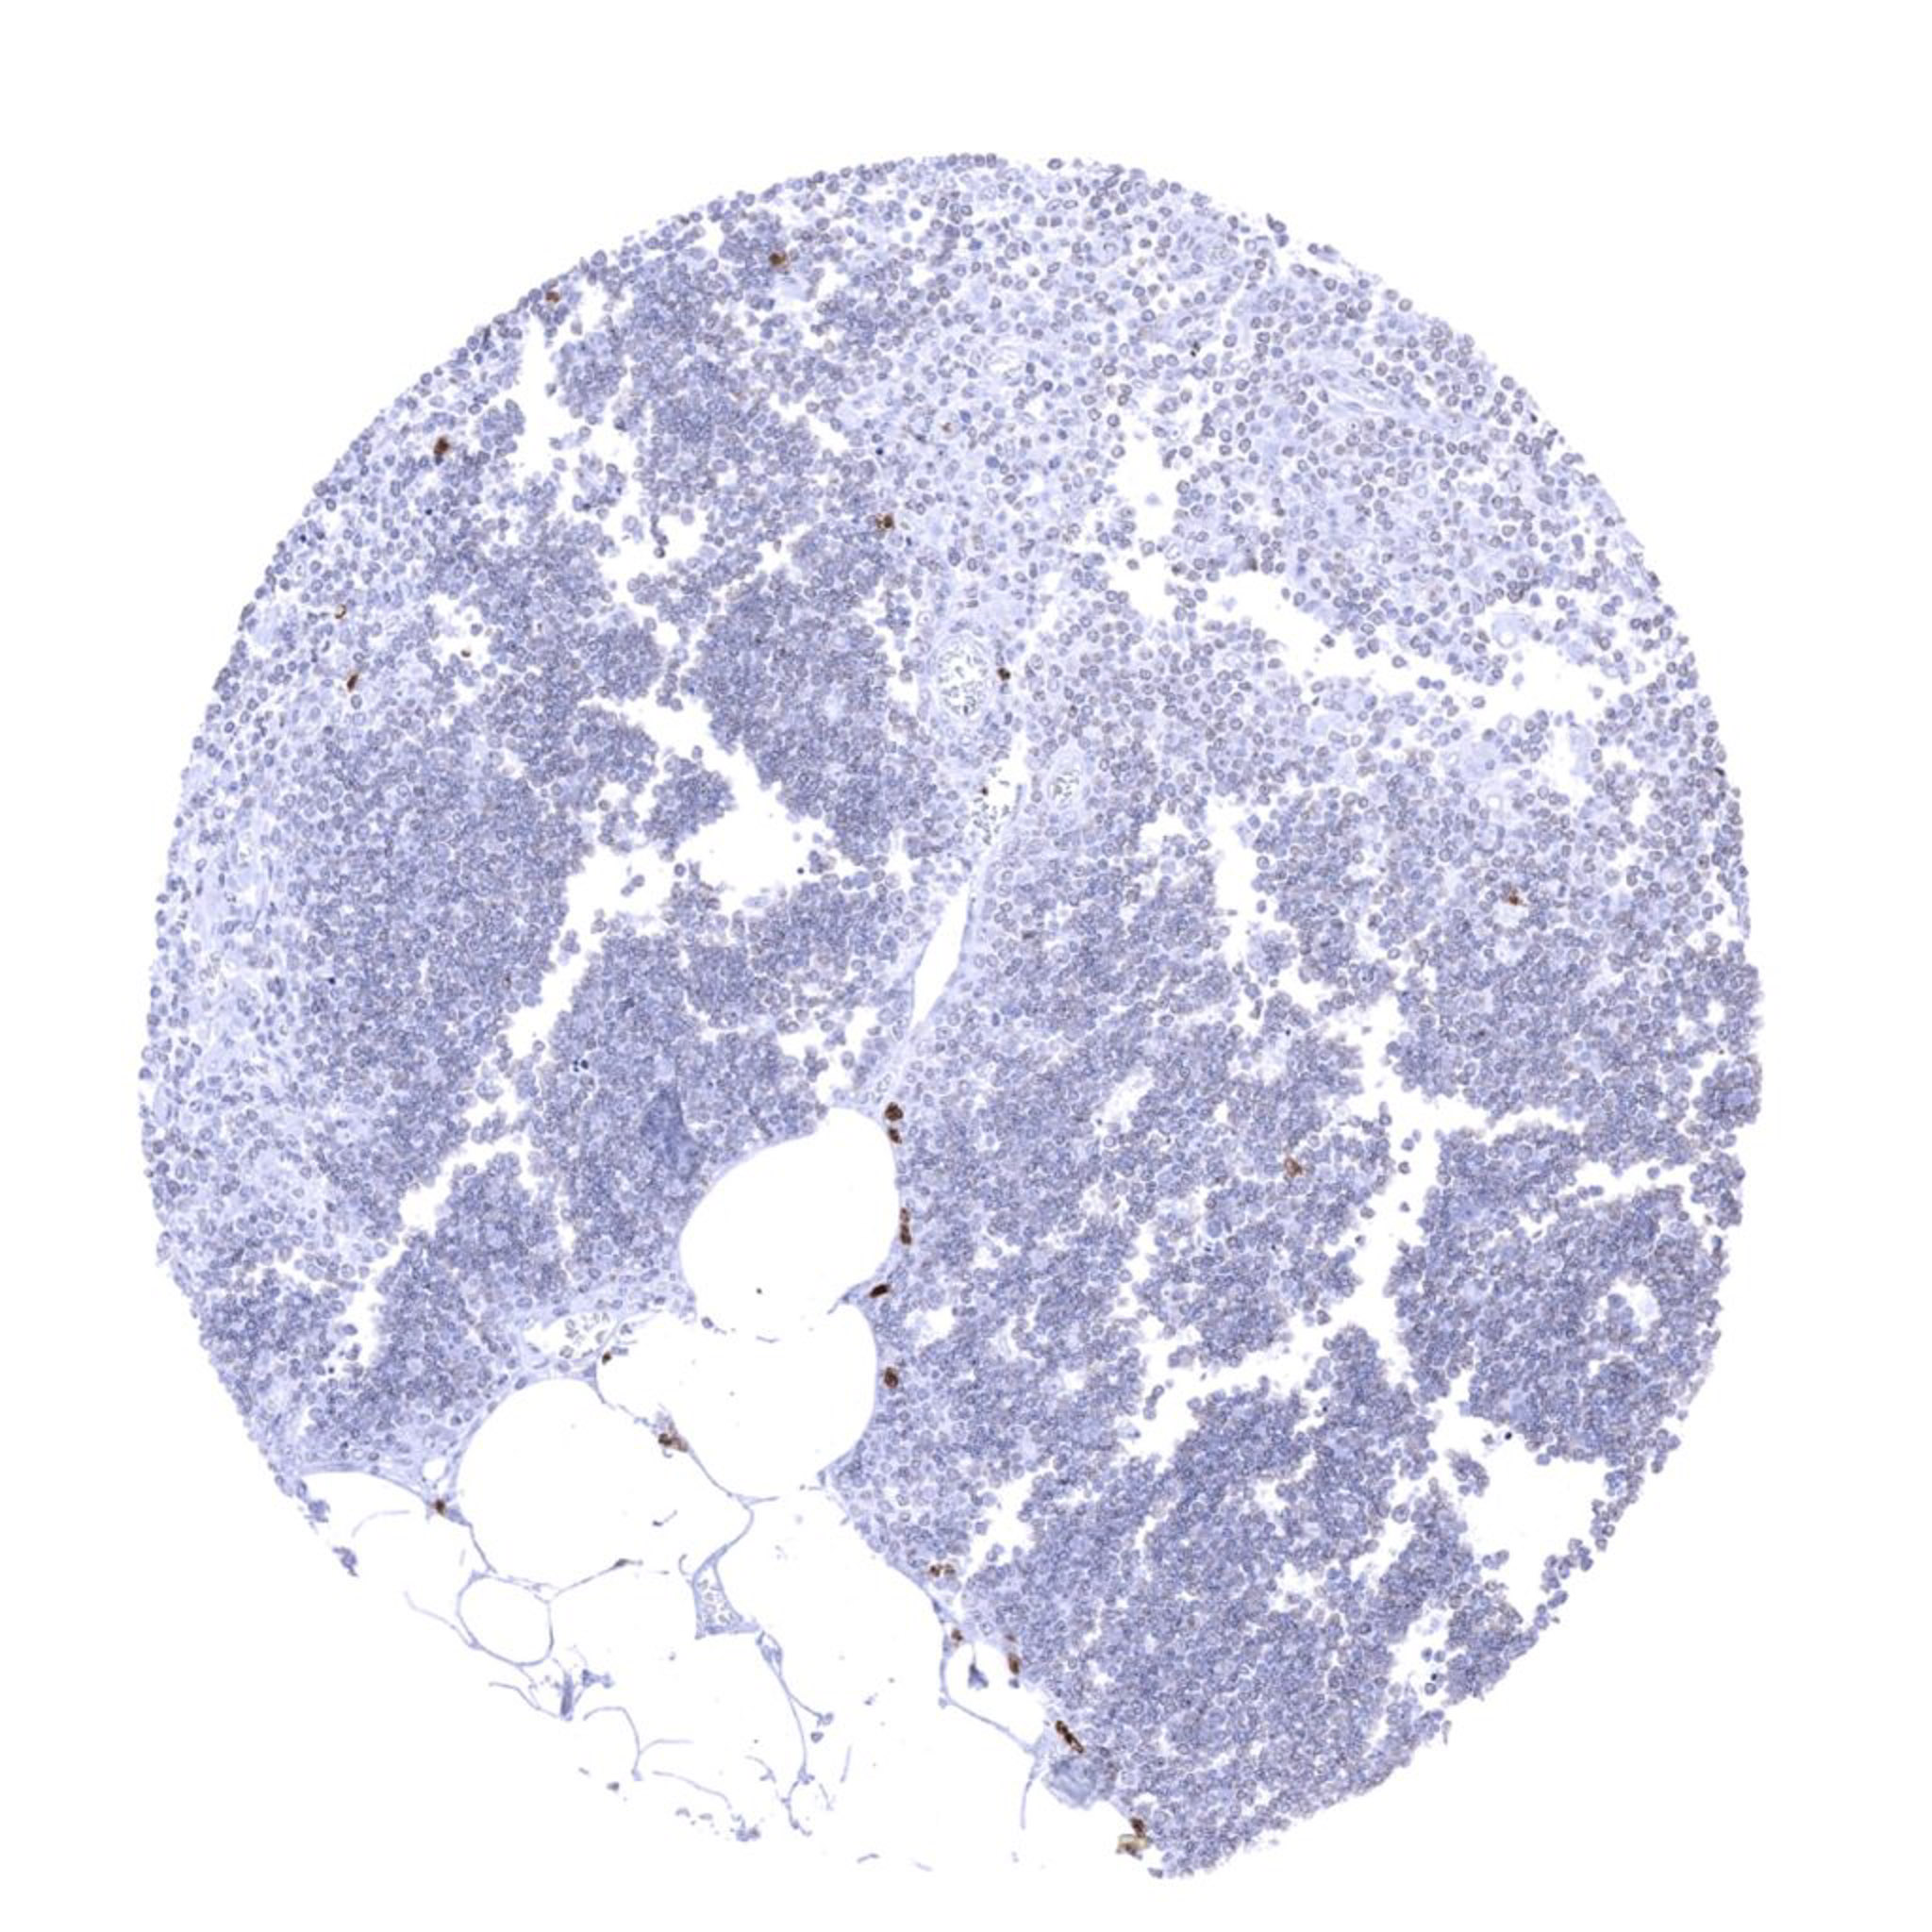

Lymph node – Few scattered granulocytes show S100A12 immunostaining.